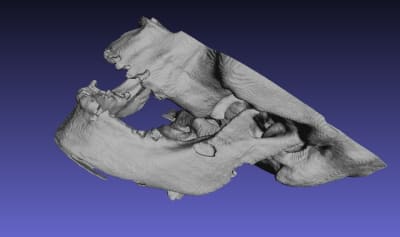

qu'est ce que vous pensez de ce guide, à mon avis il ne nécessite ni irrigation interne ni pins de rétention ( s'il est supra osseux) car rien qu'à l'aide d'un petit coup de marteau il s'enfoncera très bien sur l'Os avec une tres grande précision grace à sa structure trabéculaire.

Je vous invite à voir les autres images sur la Dropbox car elles sont très volumineuses et je n'ai pas pu les importer sur eugenol.